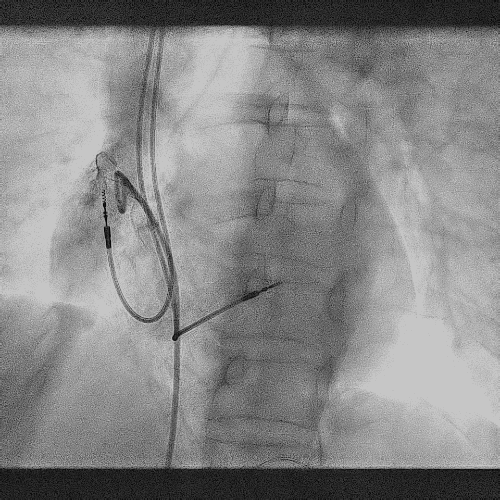

右心耳造影

拔除前进行猪尾造影,提前确认原右房导线位置为右心耳中部,心耳空间较大,解剖位置正常。为后续AVEIR™ AR植入做好计划,确认有足够空间避开原起搏导线所在位置。

RAO 30°造影

LAO 30°造影